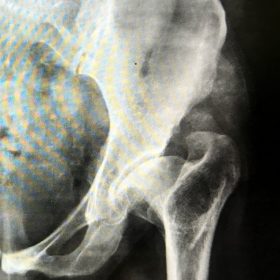

Διάγνωση- Σταδιοποίηση

Διακρίνονται σε 4 στάδια.

Στάδιο Ι. Στένωση του μεσαθριου διαστήματος

Στάδιο ΙΙ. Σκλήρυνση του υποκύμενου χόνδρου

Στάδιο ΙΙΙ. Σκλήρυνση του υπερκείμενου χόνδρου, καταστροφή του υποχόνδρινου οστούν, σχηματισμός οστεόφυτων, οίδημα αρθρώσεως και βραδυνός πόνος

Στάδιο IV. Οστική καθίζηση, καταστροφή μαλακών μορίων μυϊκών ομάδων, υπεξάρθρημα της αρθρώσεως και αλλαγή του μηχανικού άξονα